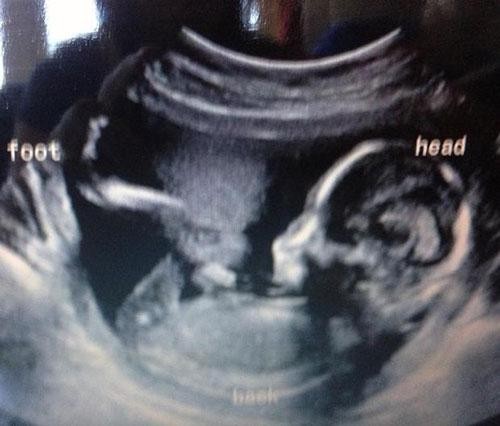

BEBEĞİN CİNSİYETİNİ ÖĞRENECEKLERDİ AMA... ULTRASONU GÖRÜNCE ŞOKE OLDULAR !

Bebeklerinin Cinsiyetlerini Öğrenmek İstediler Fakat Hayatlarının Şokunu Yaşadılar!